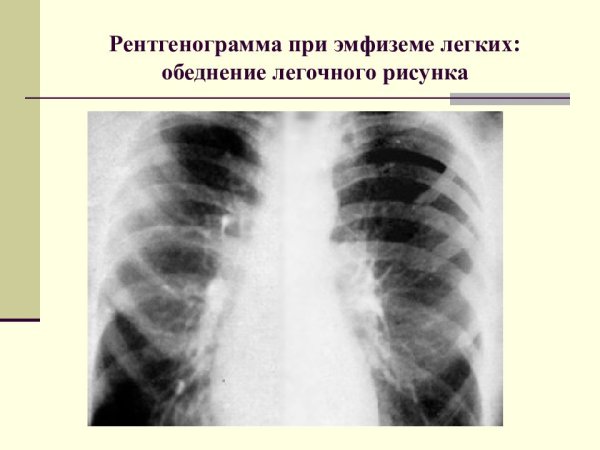

Рентгенограмма при эмфиземе легких

Обеднение легочного рисунка, или дехвитрование легочных полей, является патологическим состоянием, характеризующимся изменениями в структуре и функции легких. Это состояние часто наблюдается при различных заболеваниях дыхательной системы, таких как бронхиальная астма, хроническая обструктивная болезнь легких (ХОБЛ), фиброз легких и туберкулез. При обеднении легочного рисунка происходит уменьшение количества сосудов и альвеол, что приводит к нарушению газообмена и снижению общей эффективности дыхательной функции. Диагностика этого состояния осуществляется с помощью рентгенографии, компьютерной томографии и других методов обследования. Лечение направлено на устранение основного заболевания и восстановление нормальной структуры и функции легких, с целью повышения качества жизни пациента.